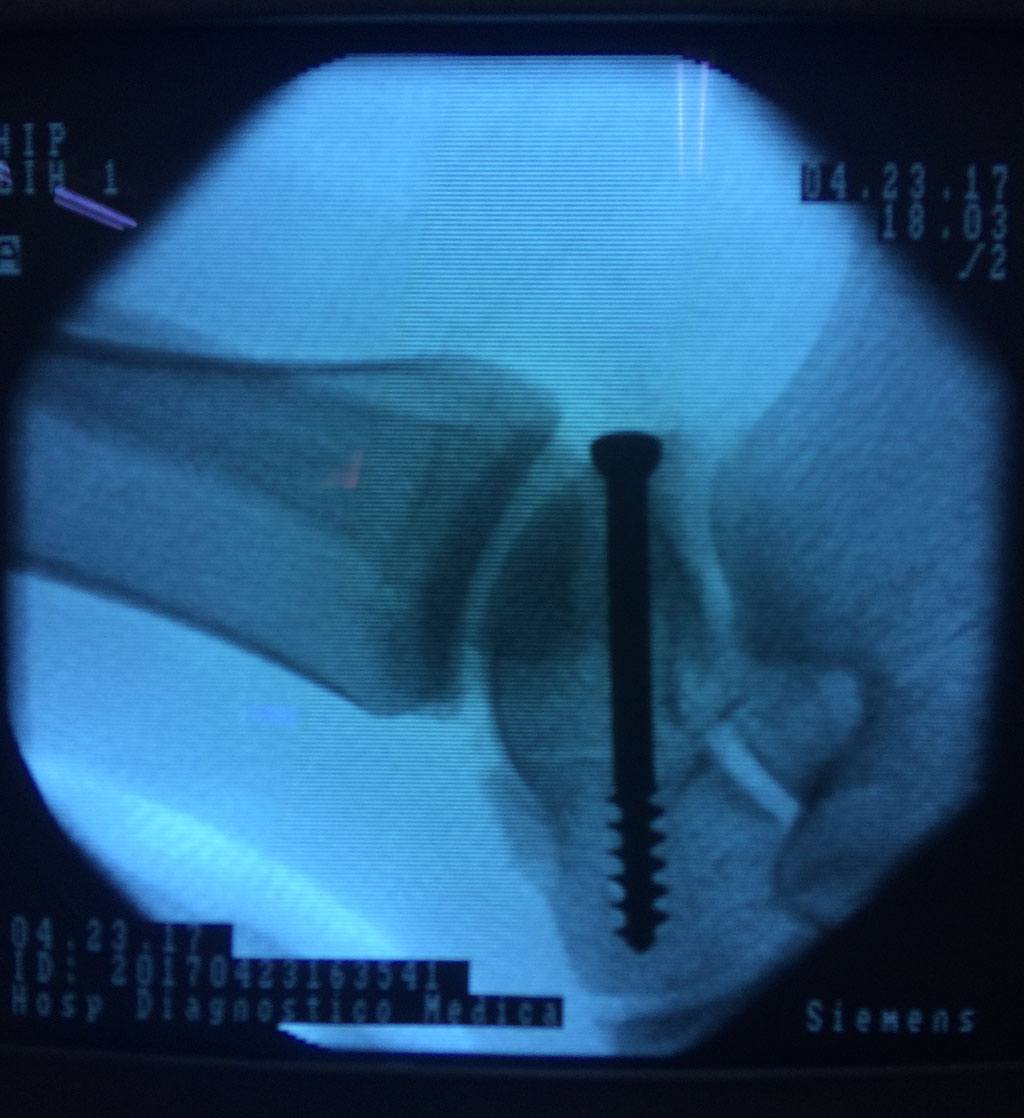

Cuando se necesita cirugía, es probable que esta implique el uso de clavijas de metal, tornillos o placas para sostener los huesos en su lugar mientras la fractura se consolida. Los elementos de soporte pueden ser temporales o permanentes.

Algunas fracturas de tobillo pueden requerir cirugía si:

- El médico cree que sus huesos probablemente no sanen apropiadamente sin cirugía.

- El médico considera que la cirugía puede permitirle una recuperación más rápida y confiable.